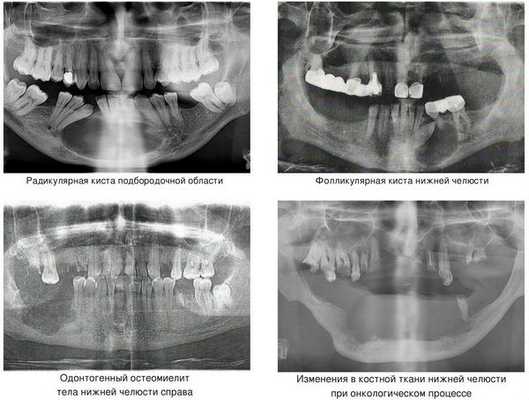

Кисты челюстей в основной массе протекают бессимптомно, медленно, но верно разрешая костную ткань. Часто патологический перелом вызвают радикулярные (корневые) и фолликулярные кисты. [2] Первые связаны с изменениями в периапикальных тканях одного или нескольких зубов, вторые являются результатом нарушения прорезывания зубов, чаще нижних зубов мудрости.

При онкологическом процессе нижняя челюсть может быть как первичным очагом, так и местом метастазирования посредством либо прорастания из близлежащих областей, либо распространением с током крови или лимфы. [3] Патологический процесс распространяется до тех пор, пока не разрушит костную ткань нижней челюсти до той стадии, в которой обычное пережевывание пищи может перевести к перелому.

Компьютерная томография (КТ) — самый информативный метод диагностики остеомиелита челюсти. Это 3D-исследование, которое позволяет определить очаг инфекции и степень выраженности воспаления, его длительность и характер. С помощью КТ можно выявить не только крупные, но и мелкие образования, единичные и групповые, а также проанализировать, насколько далеко распространилась инфекция.

В некоторых случаях в свищевой ход вводят контрастное вещество. Такой метод исследования с контрастом называется фистулографией [9] [10] .

Рентгенография в первую неделю, как правило, не выявляет изменения в кости — в этот период воспалена только верхушка корня зуба. К концу второй недели кость разрушается и становится прозрачнее.